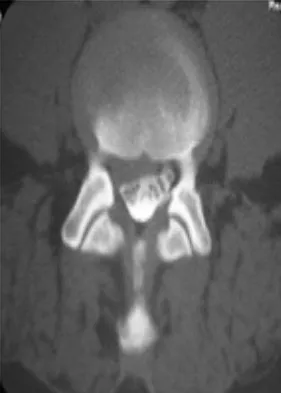

A 46-year-old woman who was involved in a motor vehicle accident reports a 4-month history of right-sided lower back pain and pain radiating into the right thigh. The patient underwent an extensive 3-month course of physical therapy and now is dependent on narcotic medication for pain control. Epidural injection therapy has failed to improve her symptoms. Examination is significant for weakness of hip flexion in the seated position and for decreased sensation to light touch in the medial anterior thigh region. Straight leg raise is negative, but the femoral stretch test reproduces anterior thigh pain. A CT myelogram image, at L3-L4, is shown in Figure 3. What is the most appropriate management at this time?

Explanation